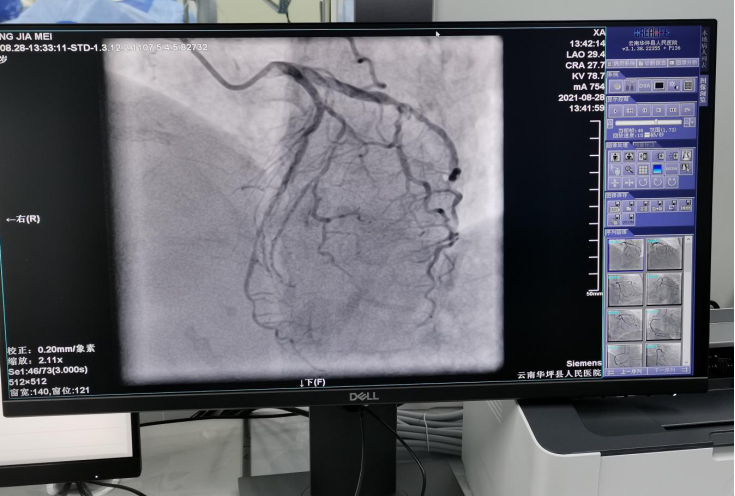

冠脉造影像一幅漂亮的“画”

在专家指导下,从8月27日到29日成功完成了20例心脏冠状动脉造影检查、5例心脏冠脉支架植入、3例颅脑动脉造影检查、2例心脏冠状动脉药物球囊植入、1例永久性心脏电生理起搏器植入,其中做了1例急诊冠状动脉造影+支架植入。所有患者在术中术后安全、平稳、顺利,痛苦较小,术后各种不适症状明显减轻。此次介入检查治疗的各项工作受到患者及家属的良好评价。